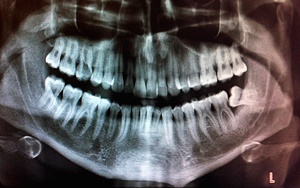

사랑니란?

우리가 사랑니라고 부르는 것은 큰 어금니 중 세 번째 위치에서 제일 마지막에 나오는 치아입니다. 사랑니가 나올 때에는 첫사랑을 하듯이 아프다고 하여 붙여진 이름이라고 하는데요. 다른 이름으로는 ‘지치’라고 합니다. 지치는 사리를 분별할 수 있는 지혜가 생긴다는 뜻입니다.

사랑니는 보통 큰 어금니와 비슷하게 생겼습니다. 사랑니의 형태나 크기는 매우 다양하다고 하는데요. 보통의 어금니 보다 깊이 나기 때문에 빼기 어렵거나 절개를 통해 힘들게 빼야 하는 경우가 많습니다. 원래 사랑니는 음식물을 갈아 내기 위한 용도라고 하는데요. 이것은 치아의 퇴화 현상이라고 생각하시는 분들도 많이 계십니다.